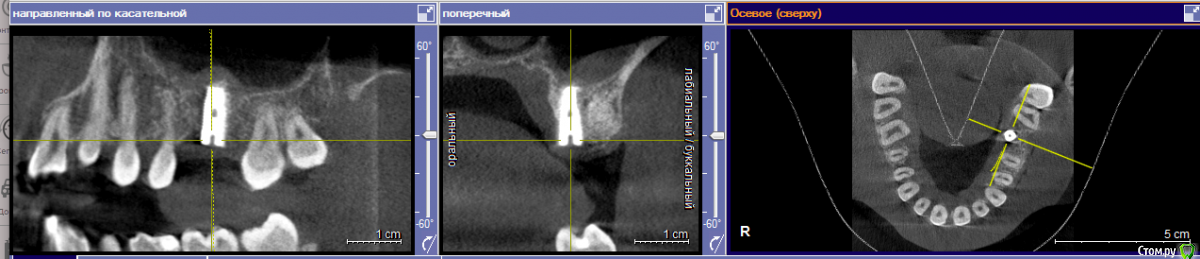

Евгений+ Опубликовано 27 июля, 2016 Поделиться Опубликовано 27 июля, 2016 Всем добрый вечер! Вчера поставил имплант, 6 сверху.Имплант смещен к небу: хирург сказал что так необходимо, т.к. зуб жевательный и нагрузка выше. Возможно ли качественное протезирование и выполнение своей функции будущим "зубом"? Ссылка на комментарий

Евгений+ Опубликовано 27 июля, 2016 Автор Поделиться Опубликовано 27 июля, 2016 (изменено) Подскажите, я правильно понимаю, что в моем случае не получится смоделировать коронку что бы центр ее оси совпадал с осью импланта? А значит, нагрузка при жевании не будет равномерно распределена вдоль оси импланта на кость. Очень настораживает наличие объема кости со стороны неба, там она вообще есть или только слизистая? Главный вопрос: оставлять или переделывать? Изменено 27 июля, 2016 пользователем Евгений+ Ссылка на комментарий

Чертков Александр Опубликовано 27 июля, 2016 Поделиться Опубликовано 27 июля, 2016 переделывать лучше 2 Ссылка на комментарий

red_butler Опубликовано 27 июля, 2016 Поделиться Опубликовано 27 июля, 2016 по свежим следам можно переставить этот же винт Ссылка на комментарий